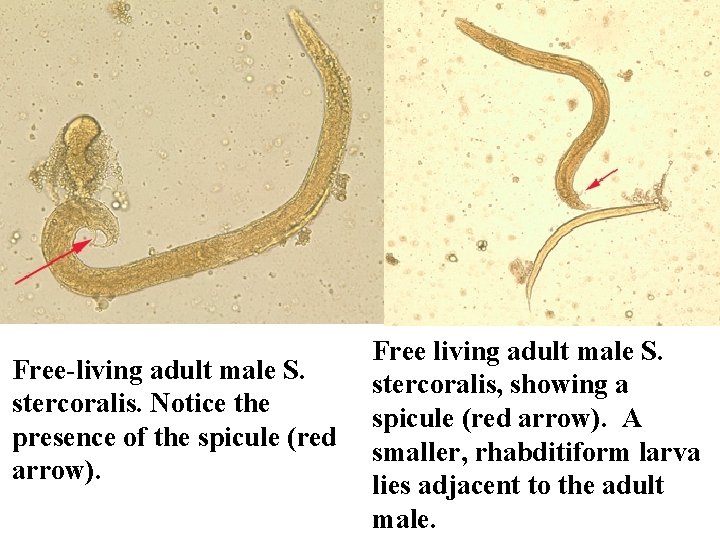

Free-living adult male S. stercoralis. Notice the presence of the spicule (red arrow). Free living adult male S. stercoralis, showing a spicule (red arrow). A smaller, rhabditiform larva lies adjacent to the adult male.